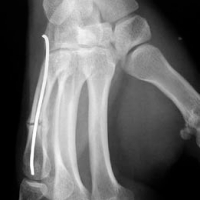

1/ Fracture du 1er métacarpien :

- fracture de Bennett ou de Rolando

2/ Fracture du 5éme métacarpien

- col ou diaphyse

- fracture du "boxeur" ou du "voyou"